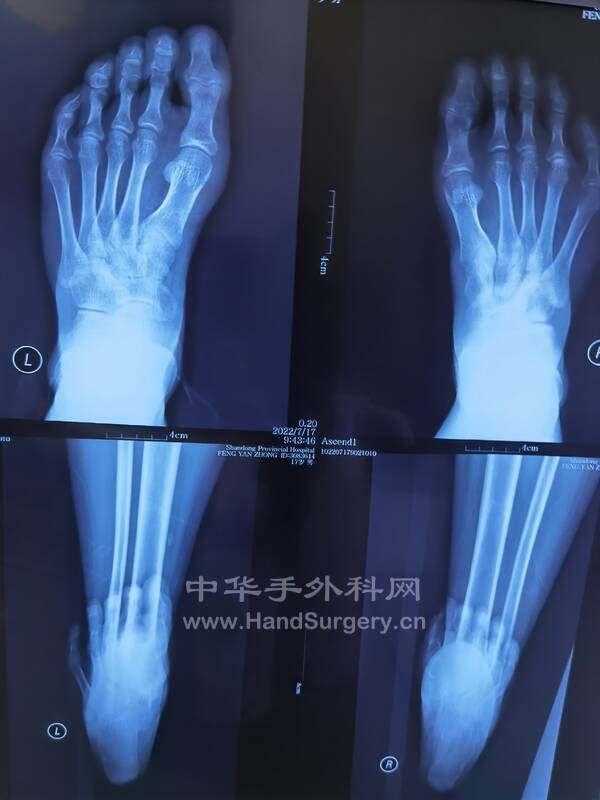

1.男,16岁双足马蹄足,儿麻后遗症,偏瘫,可行手术治疗(图1-5)

IMG_20220717_145337.jpg

IMG_20220717_145256.jpg

IMG_20220717_145332.jpg

IMG_20220717_145420.jpg

IMG_20220717_145413.jpg

IMG_20220717_160542.jpg

马蹄内翻足患者DR片:

双足正侧位(负重位),双踝正侧位(负重位),双下肢全长正位,双跟骨轴位